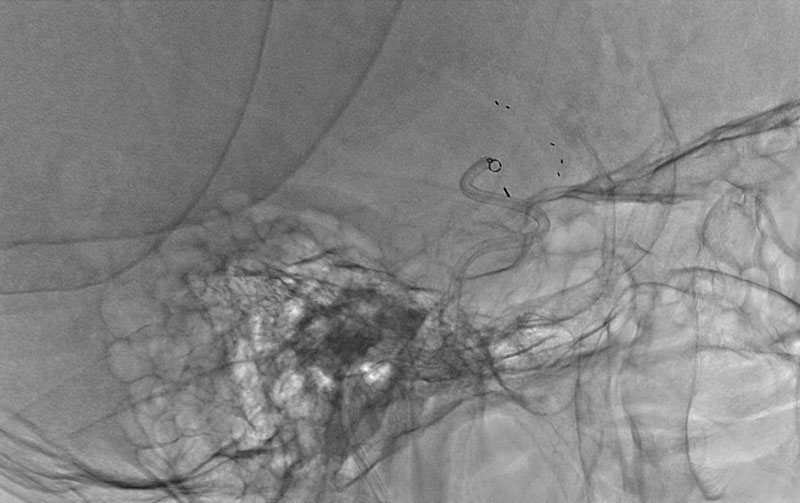

脳動静脈奇形

20代

大阪府の病院

No.1545 手術前

No.1545 手術中

No.1545 手術後